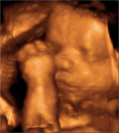

A imagem é tridimensional (3D), mas em vez de congelada como uma foto, o bebê é visto em tempo real, em movimento (4D). Além de agradar a toda a família é possível ver claramente o rosto, mãos e pés do bebê. Realizado entre 26 a 29 semanas.

Procedimentos:

Para este exame, a paciente não poderá estar em jejum.

Sua carteira pré-natal é seu documento de gestante, tenha sempre em mãos.